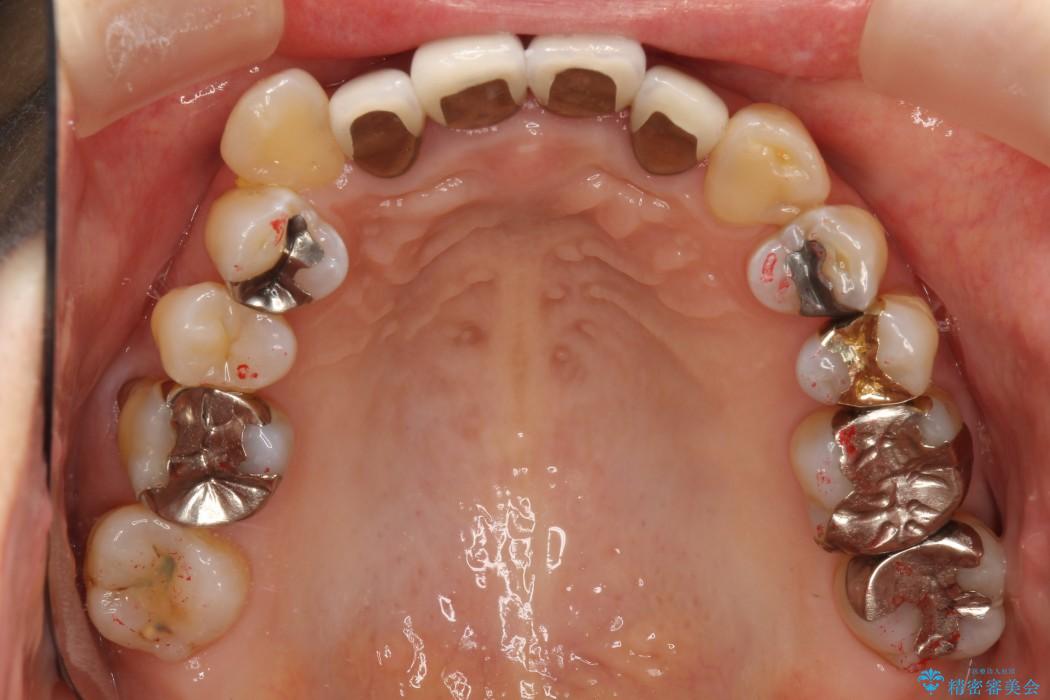

【50代女性】八重歯のインビザライン矯正 治療例

八重歯の改善を希望され来院されました。

当初はセラミックでの治療を希望されていましたが、噛み合わせと歯並びを治していく為に矯正治療を提案させていただき、インビザラインでの矯正を行う計画にしました。